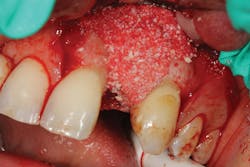

Because of this alveolar resorptive pattern after tooth extraction, bone grafting the extraction socket after tooth extraction procedures has become a solution that attempts to limit the amount of hard- and soft-tissue loss. There are many systematic reviews in the literature that compare the results of residual ridge dimension following tooth extraction after the use of a bone graft (with or without a membrane) versus extraction alone without grafting.7

What bone grafting product?

Although there are many types of grafting products commercially available, choosing the right one may be difficult. An ideal bone graft substitute should be biomechanically stable; able to degrade within an appropriate time frame; exhibit osteoconductive, osteogenic, and osteoinductive properties; and provide a favorable environment for invading blood vessels and bone-forming cells.10